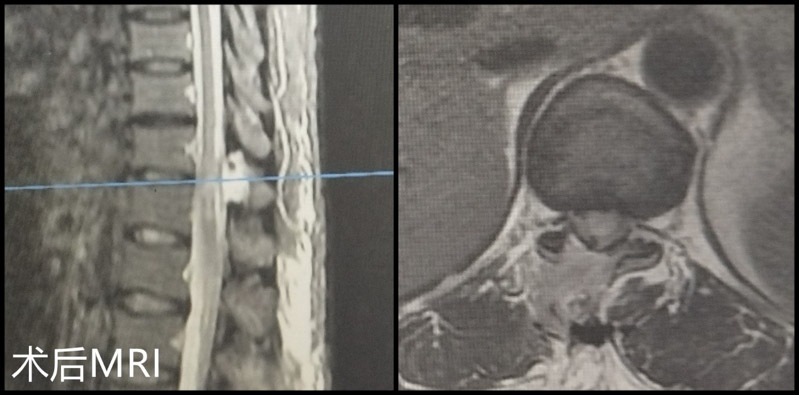

術后患者下肢雙下肢疼痛、麻木的明顯緩解,復查胸椎CT和MRI,可見手術已達到了預期的減壓效果。顏阿姨非常滿意,對醫護人員表達了衷心的感謝,目前已康復出院。